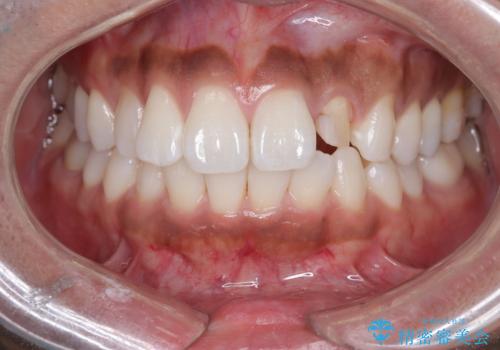

- 「前歯の歯の色が気になる」を主訴に来院された患者さんです。歯の大部分がプラスチックの材料で治療されていました。そこが劣化し変色していたためオールセラミッククラウンで治療を行いました。前歯の色を全体的に白くするために当院でオフィスホワイトニングも行いました。

左上2番の大部分がプラスチックの材料で治療されていました。そのプラスチックの材料が劣化して変色し虫歯になっている状態でした。なので古いプラスチックの材料を全て除去し、その下の虫歯を取った後、オールセラミッククラウンで治療を行いました。オールセラミッククラウンを装着する前に当院にてホワイトニングを行いました。